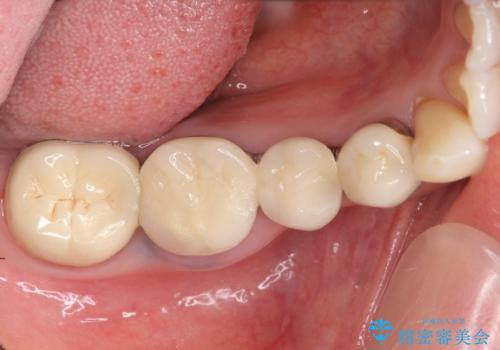

- 右下でものを咬むと痛むので診て欲しいといらっしゃった方の症例です。

右下6番目の歯を診査したところ歯根が破折していたため、保存不可能であることを説明し抜歯しました。

その後右下5、6番目にはインプラントを埋入し、右下3、4、5、6、7番の歯の補綴をオールセラミッククラウンによって行いました。

今回用いたオールセラミッククラウンはジルコニアフレームという白い素材の上にセラミックを盛っているため、審美性が非常に高いのが特徴です。

また、ジルコニアは人工ダイヤモンドの材料にも使われているほど高い強度を持っており、そのためオールセラミッククラウンは審美性だけでなく、奥歯やブリッジの補綴も可能とするクラウンです。